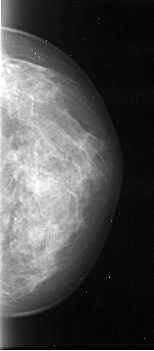

A_1096_1.RIGHT_MLO

RIGHT_MLO LINES 4936 PIXELS_PER_LINE 1786 BITS_PER_PIXEL 16 RESOLUTION 42 NON_OVERLAY